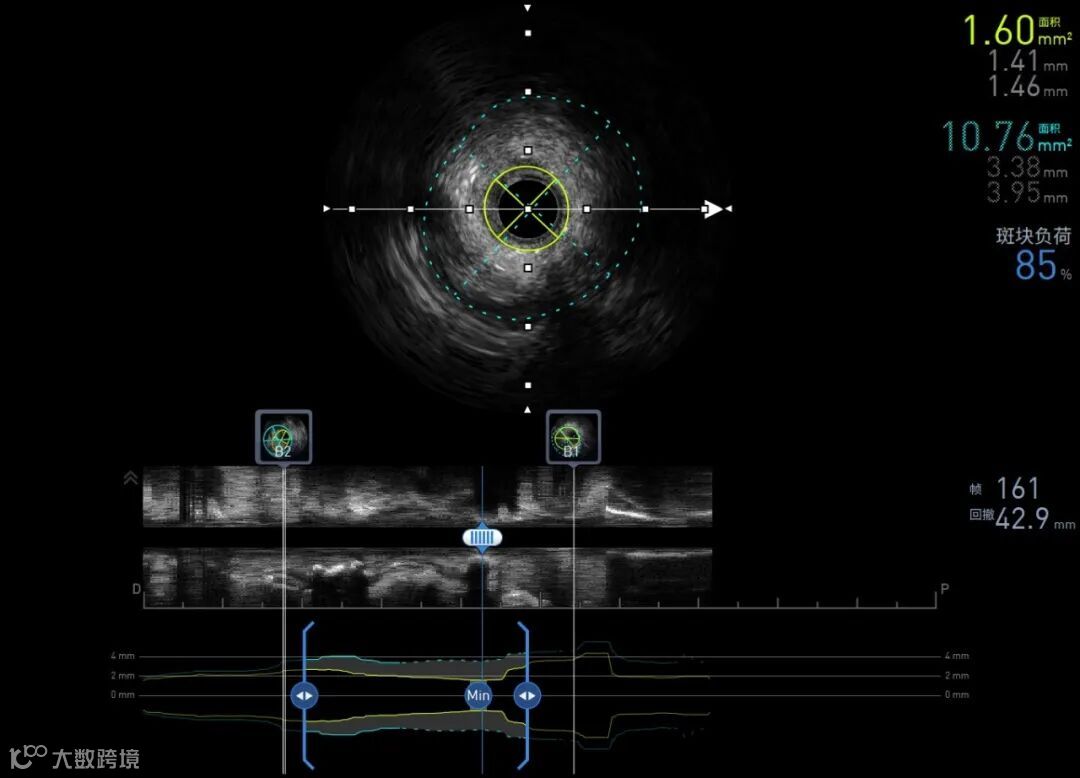

60MHz 术前LCX

pullback speed 0.5 mm/s

ALA展示血管辅助测量结果